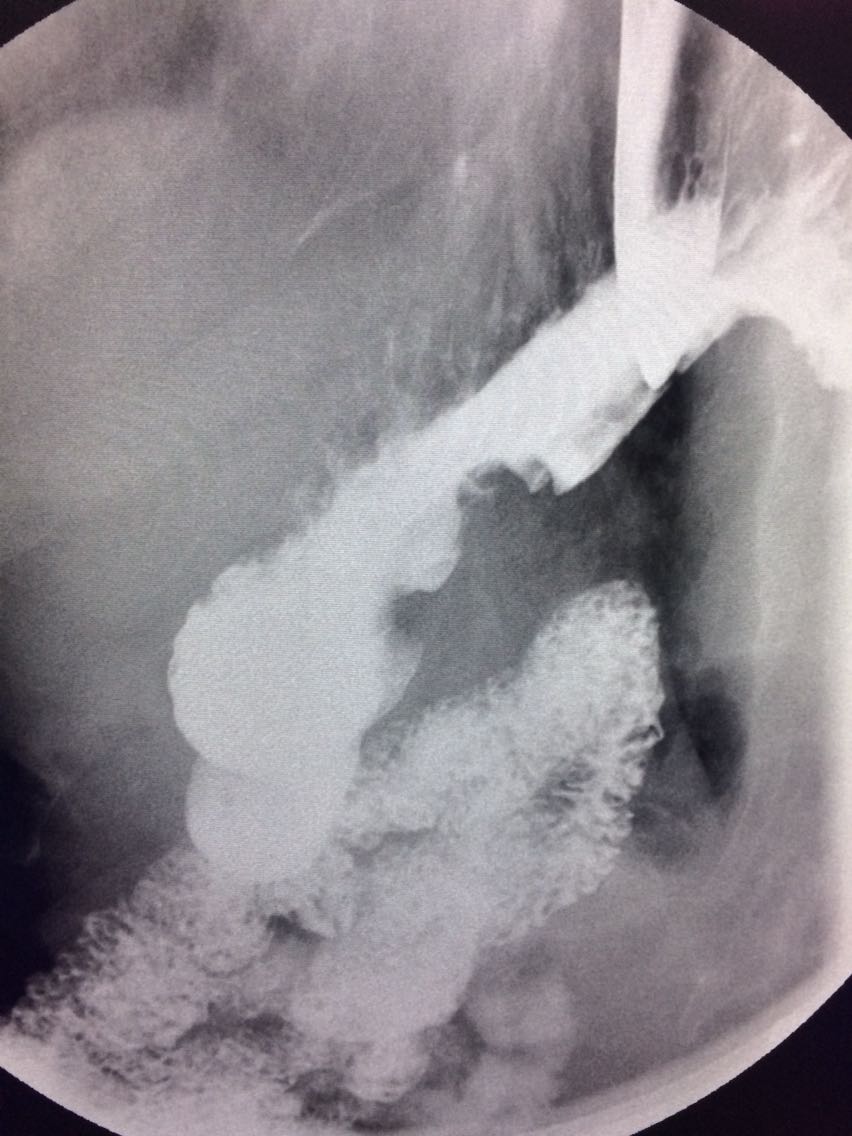

一例溃疡型胃癌。

男,45岁 反复胃疼5年余。 5年来,反复出现胃疼,进食后半小时加重,经常感觉饥饿,当地按胃溃疡,给予阿莫西林,奥美拉唑治疗,具体不详,效果欠佳,遂入院,入院来,饮食睡眠,二便可。 既往体健。 入院上消化道造影如图。

如图

讨论,诊断及鉴别诊断? 胃溃疡的影像表现? 溃疡良恶性的鉴别? 入院后行胃大部切除术。 诊断,胃腺癌。